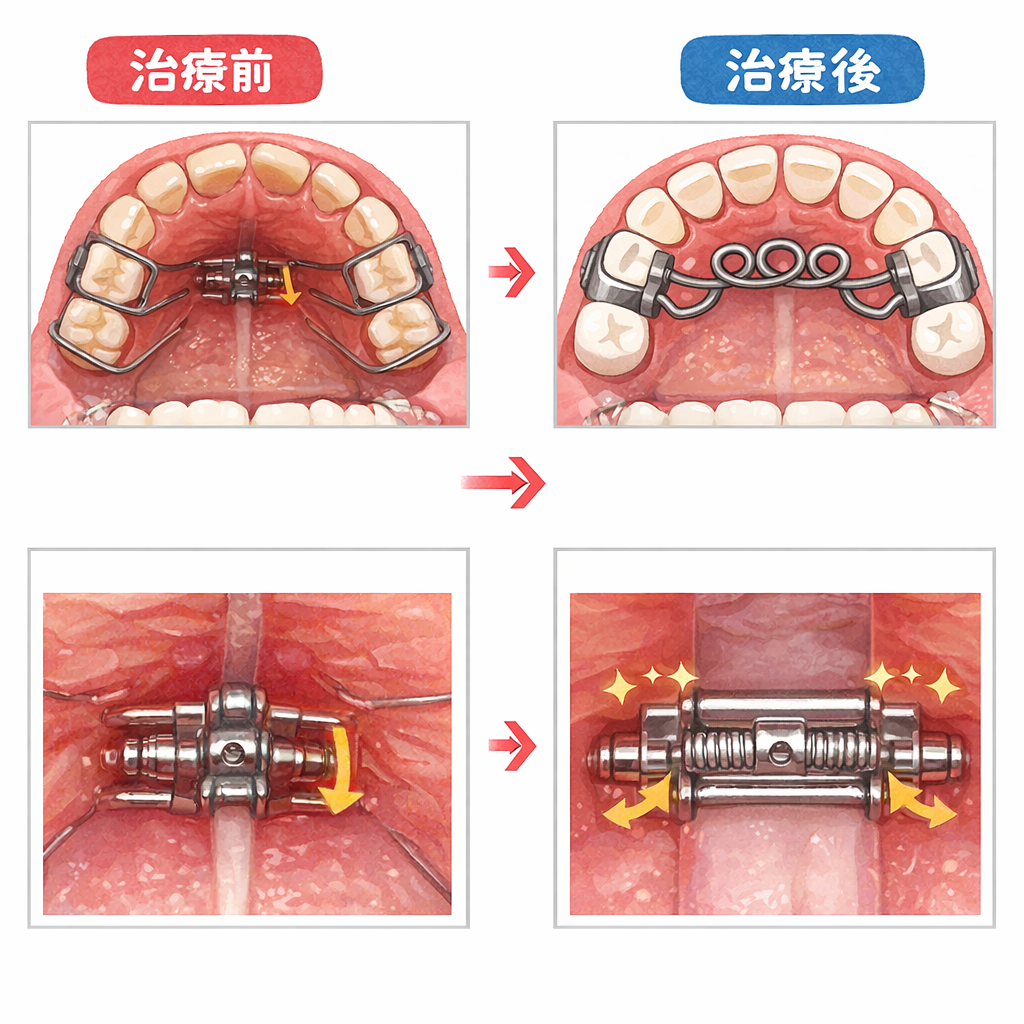

●急速拡大装置

急速拡大装置は、接着剤で歯にくっつける固定式の拡大装置です。

急速拡大装置は強い力が発揮できる拡大装置で、上顎の骨そのものを広げます。

●形

急速拡大装置は、歯にくっつける金属製のバンド・バンドからのびる太めのワイヤー・左右のワイヤーをつなげている拡大ネジから作られています。

●使い方

急速拡大装置の真ん中についているネジを術者が回します。

すると、太いワイヤーが左右に広がります。

一般的には1日にネジを1/4回転させます。

すると、0.2mmほど左右に広がります。

これを毎日繰り返し、1~3ヶ月程度の時間をかけて、顎の骨の横幅を広げていきます。

横幅が十分広がったら、それ以上はネジを回す必要はありません。

ですが、すぐに取り外すわけではなく、顎の骨が安定するまでさらに6ヶ月程度装着したままにします。